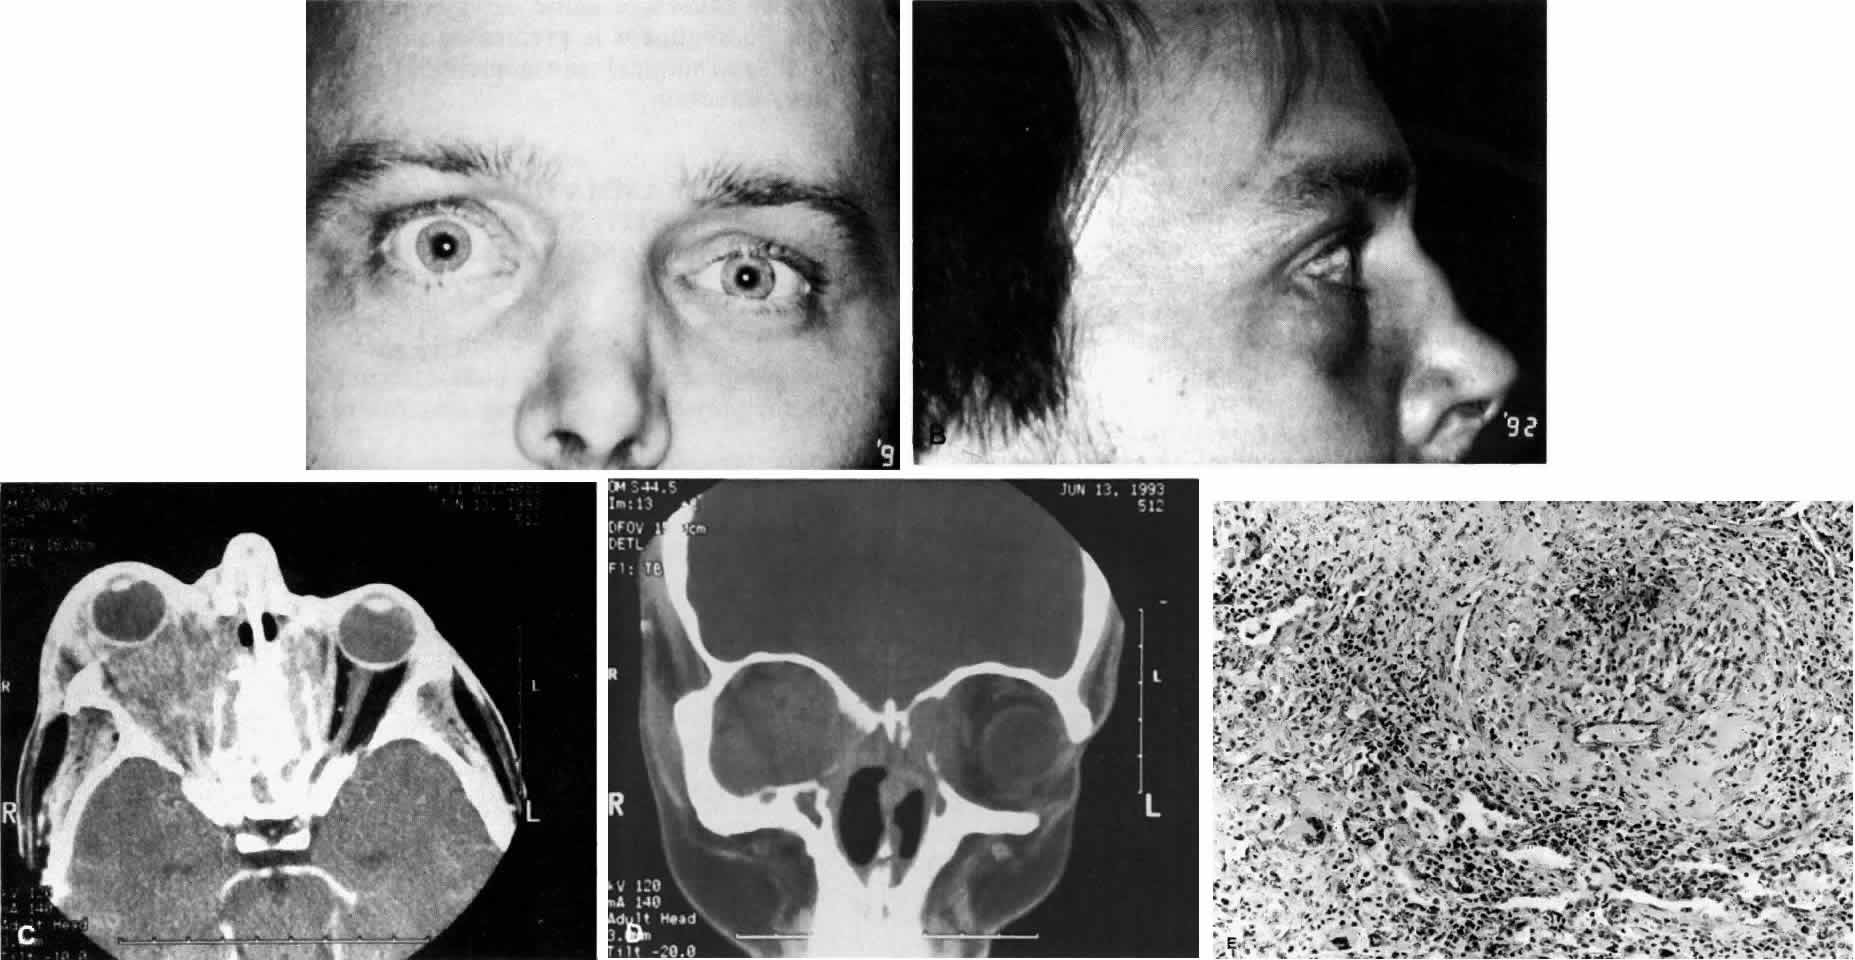

POLYARTERITIS NODOSA

Polyarteritis nodosa is a vasculitic disease of medium-sized and small blood vessels whose description is attributed to von Rokitansky and to Kussmaul and Maier.191,192 The blood vessels of the kidney, bowel, skin, muscle, heart, nervous system, and eye may be involved (Fig. 12), but unlike Wegener's granulomatosis and lymphomatoid granulomatosis, the pulmonary vessels are usually spared.

Fig. 12. Polyarteritis nodosa. Mesenteric artery from patient with exophthalmos manifests massive mural inflammation with necrosis of muscularis (H&E, ×208).

Ocular Manifestations

Ocular blood vessels may be primarily affected by vasculitis or may demonstrate the secondary effects of severe hypertension that accompanies renal involvement. The choroidal, posterior ciliary, and retinal vessels are most frequently affected.3 As in other organs, retinal vasculitis results in vascular occlusion or aneurysm. Choroiditis, scleritis, peripheral ulcerative keratitis, conjunctival vasculitis, and uveitis also occur.156,197–200 Orbital involvement can present as exophthalmos201–203 and may be the initial sign of polyarteritis nodosa.204 The extraocular muscles and optic nerves may be involved.3 It has been suggested that the orbital inflammation may be contiguous with adjacent sinusitis.205 The presence of bilateral orbital pseudotumor suggests a systemic disease, and polyarteritis nodosa must be considered.

The remaining two criteria are angiographic findings and biopsy findings from an affected organ system. Angiography demonstrates aneurysms or occlusions of vessels. Muscle, nerve, testicle, liver, kidney, and skin may be biopsied and examined for granulocytic and/or mononuclear involvement of the wall of small and medium-sized muscular arteries.193,206–208

Because lesions are segmental and may scar as they become chronic, orbital biopsy may not demonstrate classic lesions of polyarteritis nodosa with full-thickness involvement of the small and medium-sized arteries, fibrinoid necrosis, and edema. Nonetheless, perivascular inflammation without inflammation elsewhere on the biopsy specimen and the presence of eosinophils are suggestive findings. Granulomatous changes and the presence of giant cells are not characteristic and should raise the possibility of alternate diagnoses.3